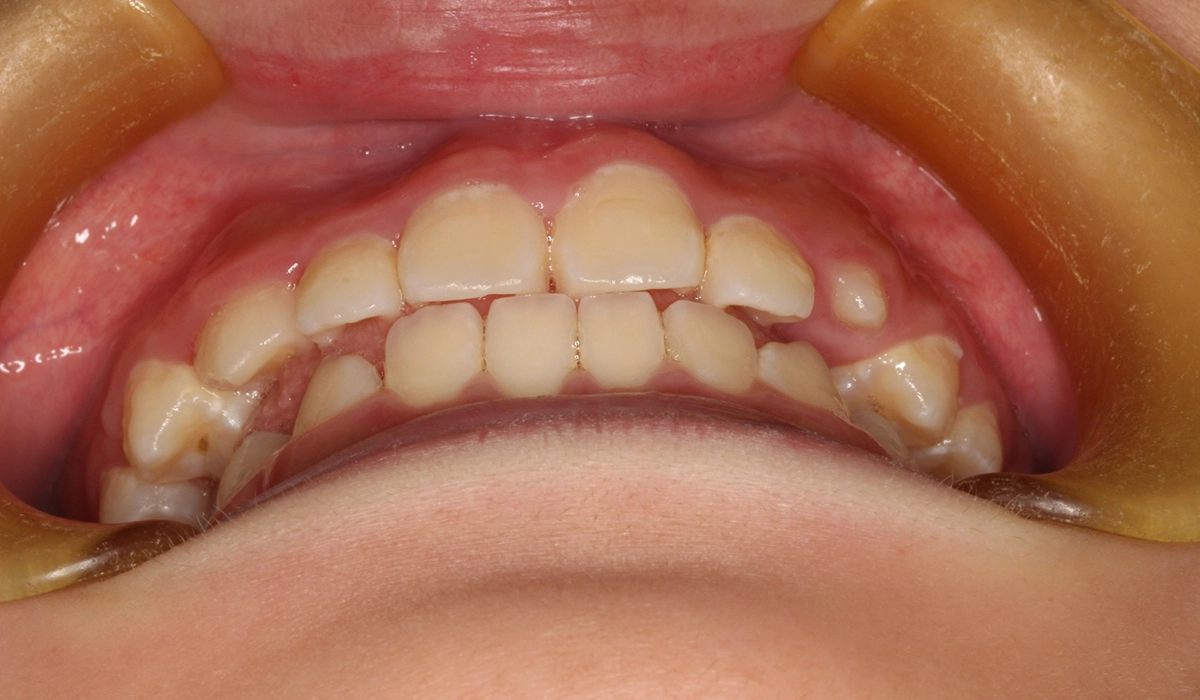

今回ご紹介する患者様は、前歯の捻れを気にされており、矯正検査後叢生Ⅰ級と診断いたしました。

主訴 前歯の捻れが気になる

治療期間 70カ月

治療費用 453,600円(税込)※2019年時治療費

治療内容 前歯の捻れを気にされており、矯正検査後叢生Ⅰ級と診断いたしました。